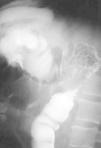

En la exploración el abdomen estaba distendido, con ligera defensa en la fosa ilíaca derecha. El peristaltismo estaba aumentado. El tacto rectal no mostraba masas y la prueba de sangre oculta en heces fue negativa. Se rea-lizó una radiografía de abdomen simple que mostró una importante distensión de todo el marco cólico derecho y ciego. En la analítica se apreciaba leucocitosis de 18,5 x 109/l, con un 90% de polimorfonucleares. Las concentraciones de amilasa y lipasa en suero fueron normales. Se realizó un enema con contraste que mostró una estenosis del ángulo esplénico indicativa de neoplasia, aunque el análisis exhaustivo de la radiografía puso de manifiesto una morfología de la mucosa conservada (fig. 1). Con la orientación diagnóstica de neoplasia oclusiva, se indicó laparotomía urgente durante la que se apreciaron múltiples adherencias y una distensión masiva de todo el colon transverso y derecho, así como isquemia del ciego. Se encontró una tumoración en la flexura esplénica del colon que infiltraba el hilio esplénico y que causaba la oclusión. La cola del páncreas parecía indurada pero no infiltrada por la tumoración. Ante estos hallazgos, se optó por realizar una colectomía subtotal y una esplenectomía en bloque con una anastomosis laterolateral mecánica entre el íleon distal y el sigma. El postoperatorio inmediato se complicó con una neumonía basal derecha que se trató con amikacina y ceftacidima, con buena evolución posterior. Se inició dieta oral en el sexto día postoperatorio, con buena tolerancia, y se dio de alta al paciente el duodécimo día postoperatorio.

Fig. 1. Enema con contraste que muestra una estenosis irregular de la flexura esplénica indicativa de neoplasia.